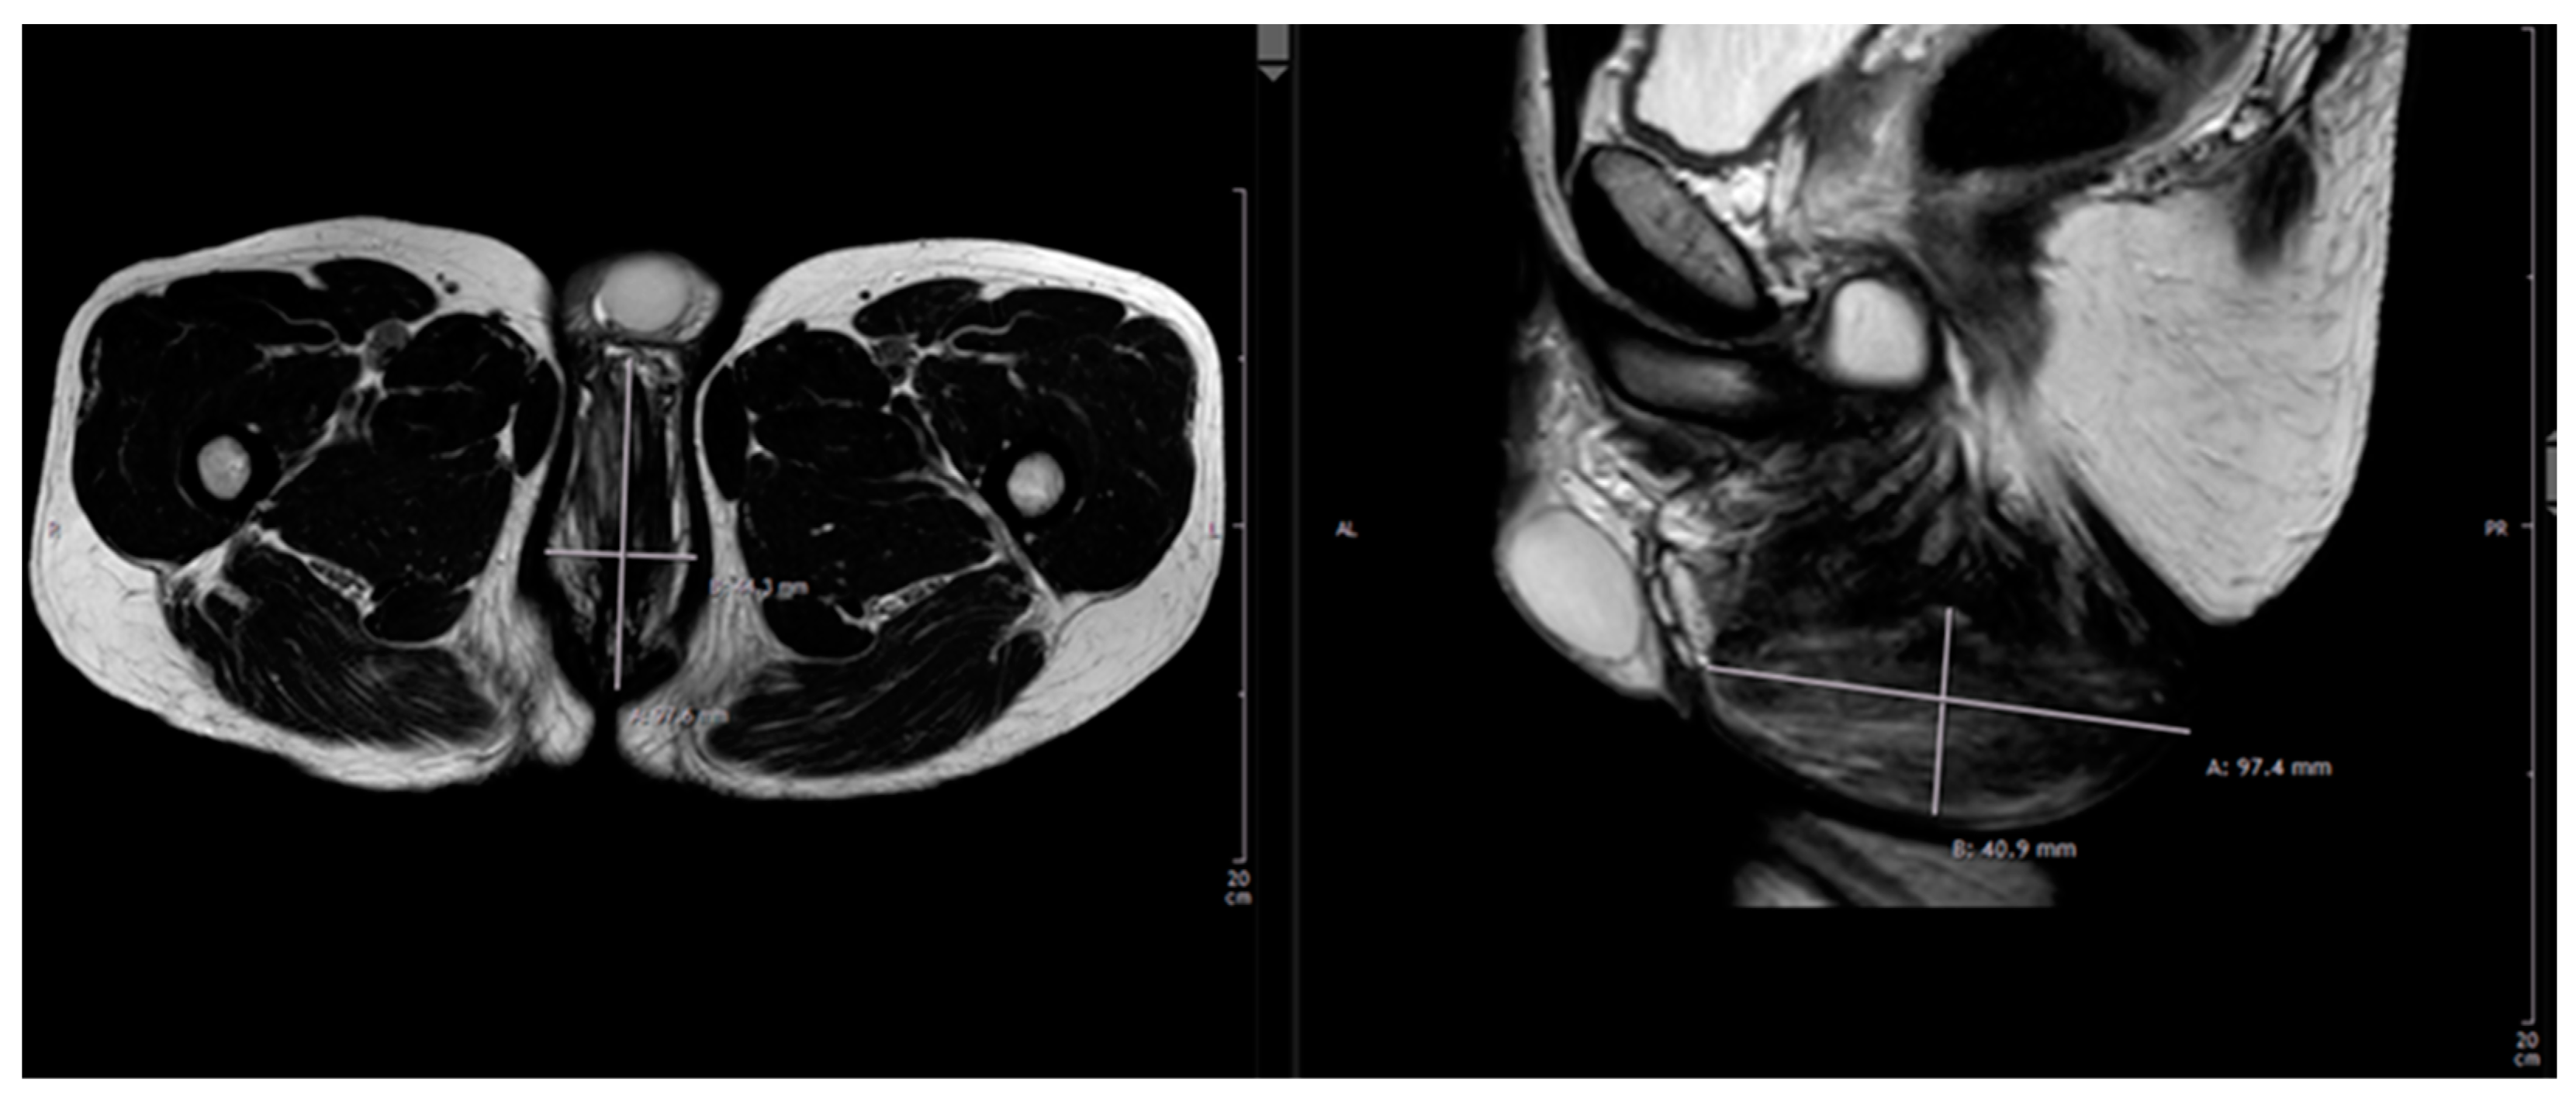

Presentation of our department’s experience in the context of PNI: A 42-year-old, otherwise healthy, male presented to our department of plastic surgery upon referral from the department of urology with a 10-year history with a nodular perineal lesion. He reported a progression of the swelling over the years, with the development of a small, non-healing, secreting wound becoming prominent in the past few months. At the time of presentation at our department, he was road cycling between 10–15 h weekly on a semi-professional basis and felt increasingly impaired by the tissue proliferation. The patient denied any sensibility impairment, erectile dysfunction or dysuria. Physical examination revealed a 12 × 6 × 4.5 cm large, mobile, non-tender, partially fibrotic mound of perineal tissue. On the base of the tumor there was a 3 mm small, sharply demarcated, circular secreting ulceration (see Figure 1). Ultrasonography revealed a mass of hypoechoic tissue with singular hyperechoic lesions and sparse perfusion inferior to the raphe, with no testicular abnormalities. Native and contrast enhanced T2-weighted MRIs demonstrated a non-homogenous soft tissue proliferation with unclear demarcation to the surroundings, which was classified as a diffuse, partially fibrotic tissue transformation (see Figure 2). The patient history and clinical findings pointed to the diagnosis of an extensive cyclist’s nodule with fibrosis related disruption of lymphatic drainage. Considering the available literature and the size of the lesion, we recommended surgical excision with tissue doubling and optional lymph vessel obliteration assisted by intraoperative ICG-monitoring in inpatient setting.

Figure 2. Diagnostic imaging: native and contrast enhanced T2-weighted MRI demonstrated a non-homogenous soft tissue proliferation with unclear demarcation to the surroundings, which was classified as a diffuse, partially fibrotic tissue transformation.